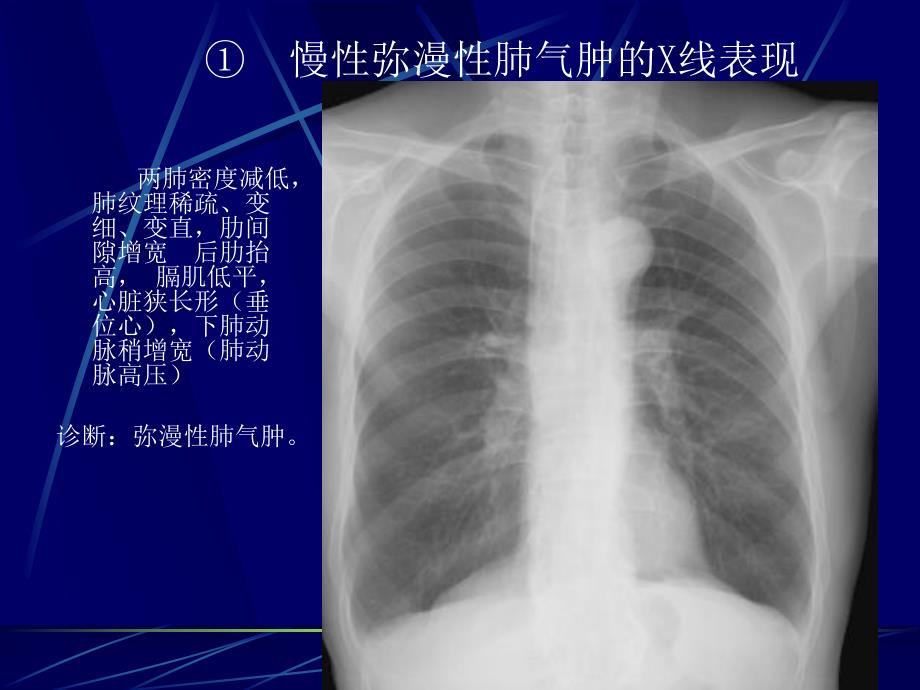

1、呼吸系统基本病变影像表现1.支气管阻塞支气管阻塞有哪些原因支气管不完全阻塞,相应肺叶会出现什么改变?支气管完全阻塞,相应肺叶会出现什么改变?慢性弥漫性肺气肿的X线表现 两肺密度减低,肺纹理稀疏、变细、变直,肋间隙增宽 后肋抬高,膈肌低平,心脏狭长形(垂位心),下肺动脉稍增宽(肺动脉高压)诊断:弥漫性肺气肿。两肺密度减低,左肺明显且肺纹理稀疏、变细、变直,两下肺野见多个无壁及薄壁不规则囊状气腔,CT显示较清楚。膈肌低平,两侧肋膈角变钝。诊断:弥漫性肺气肿并肺大泡。局限性肺气肿右肺中叶密度减低,中叶支气管稍变窄。右肺中叶肺气肿左侧肺野密度减低,纵隔向右侧移位。诊断:左侧肺气肿左肺密度减低,纵隔向右